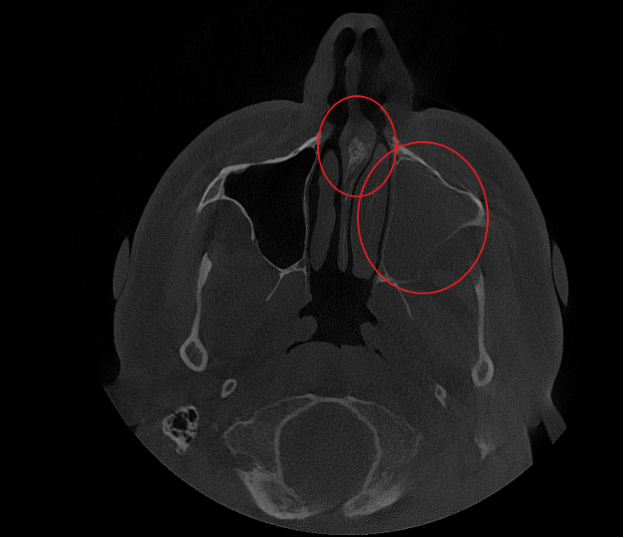

- Компьютерная томография (КЛКТ) околоносовых пазух и височных костей: Этот высокоинформативный метод диагностики объективно показал искривление носовой перегородки вправо, субтотальное снижение пневматизации (воздушности) левой верхнечелюстной пазухи, что свидетельствовало о хроническом воспалительном процессе. Костно-деструктивных изменений не выявлено.

Послеоперационный период протекал гладко. Проводились регулярные туалеты полости носа, промывание оперированной пазухи, назначались средства для увлажнения и регенерации слизистой оболочки, а также местная антибактериальная терапия. По результатам оперативного лечения носовое дыхание было полностью восстановлено, признаки активного воспаления купированы. Спустя 1.5 месяца после проведенного оперативного лечения проведено КТ околоносовых пазух в динамике, что отражает промежуточный результат оперативного лечения. На снимках: Перегородка носа располагается по центру, оперативно созданное соустье левой верхнечелюстной пазухи функционирует, пневматизация левой верхнечелюстной пазухи значительно улучшилась. Окончательный результат можно будет оценить через 3 месяца после проведенной операции, и при полной пневматизации левой верхнечелюстной пазухи пациент сможет приступить к установке зубных имплантов в верхнюю челюсть слева.